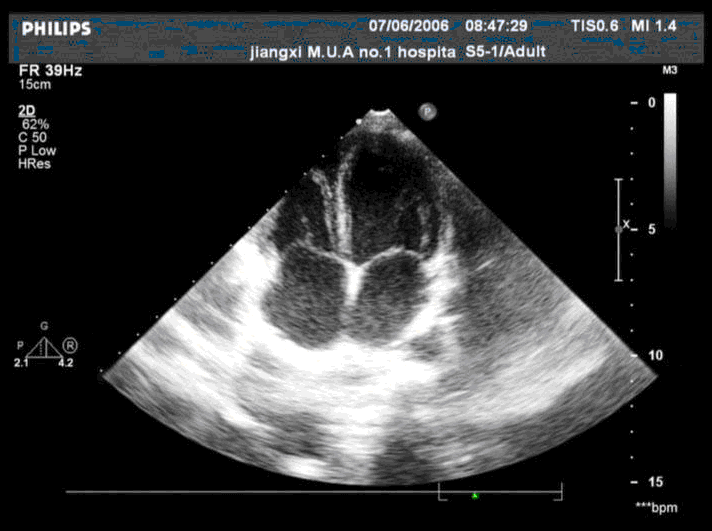

超声检查如图,该切面为哪种超声心动图切面 CF20160315_38.gif

• A.心尖四腔

• B.心尖短轴

• C.左室长轴

• D.心尖二腔

• E.大动脉短轴